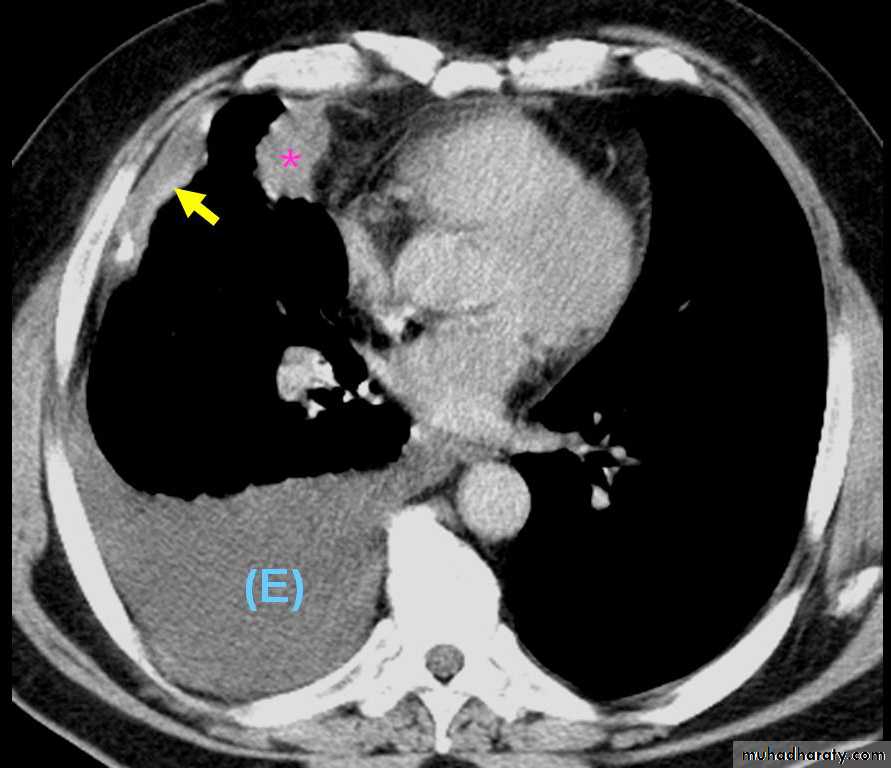

3-CT scanning displays pleural abnormalities more readily than either plain radiography or ultrasound, and may distinguish benign from malignant pleural disease.

Computed tomography scan of the chest demonstrates a mass in the right upper lobe adjacent the pleura (*). Irregular soft-tissue thickening of the pleural surface (arrow) and pleural effusion (E) are present. The findings are most consistent with primary lung neoplasm with pleural metastasis and malignant pleural effusion. Results of thoracentesis were positive for malignant cells (adenocarcinoma).